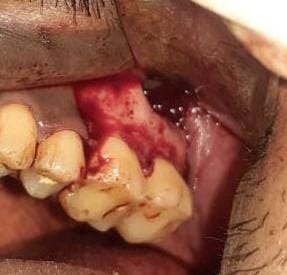

Incision and drainage was done.

Biopsy sample sent